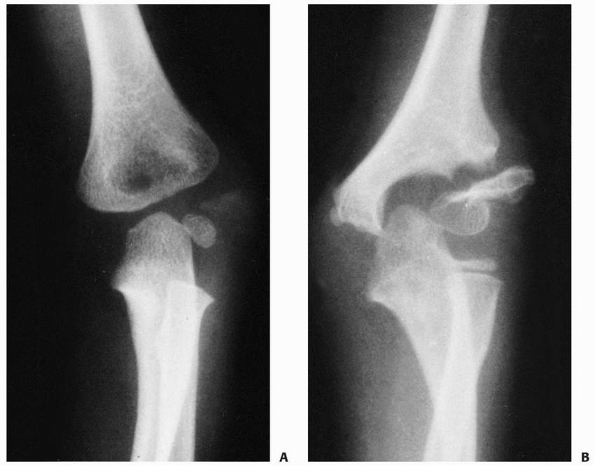

![]() |

FIGURE 15-26 Fracture of the capitellum in a 13-year-old girl. A.

Injury film, lateral view, shows the large capitellar fragment lying anterior and proximal to the distal humerus. Both the radiocapitellar (solid arrow) and trochlear grooves (open arrow) are seen in the fragment. B. In the AP view, only a faint outline of the fragment is seen (arrows). |

FIGURE 15-27 A,B. Fracture of the capitellum in a 14-year-old boy. C,D. After open reduction and fixation with two small cannulated screws through a lateral approach.

|